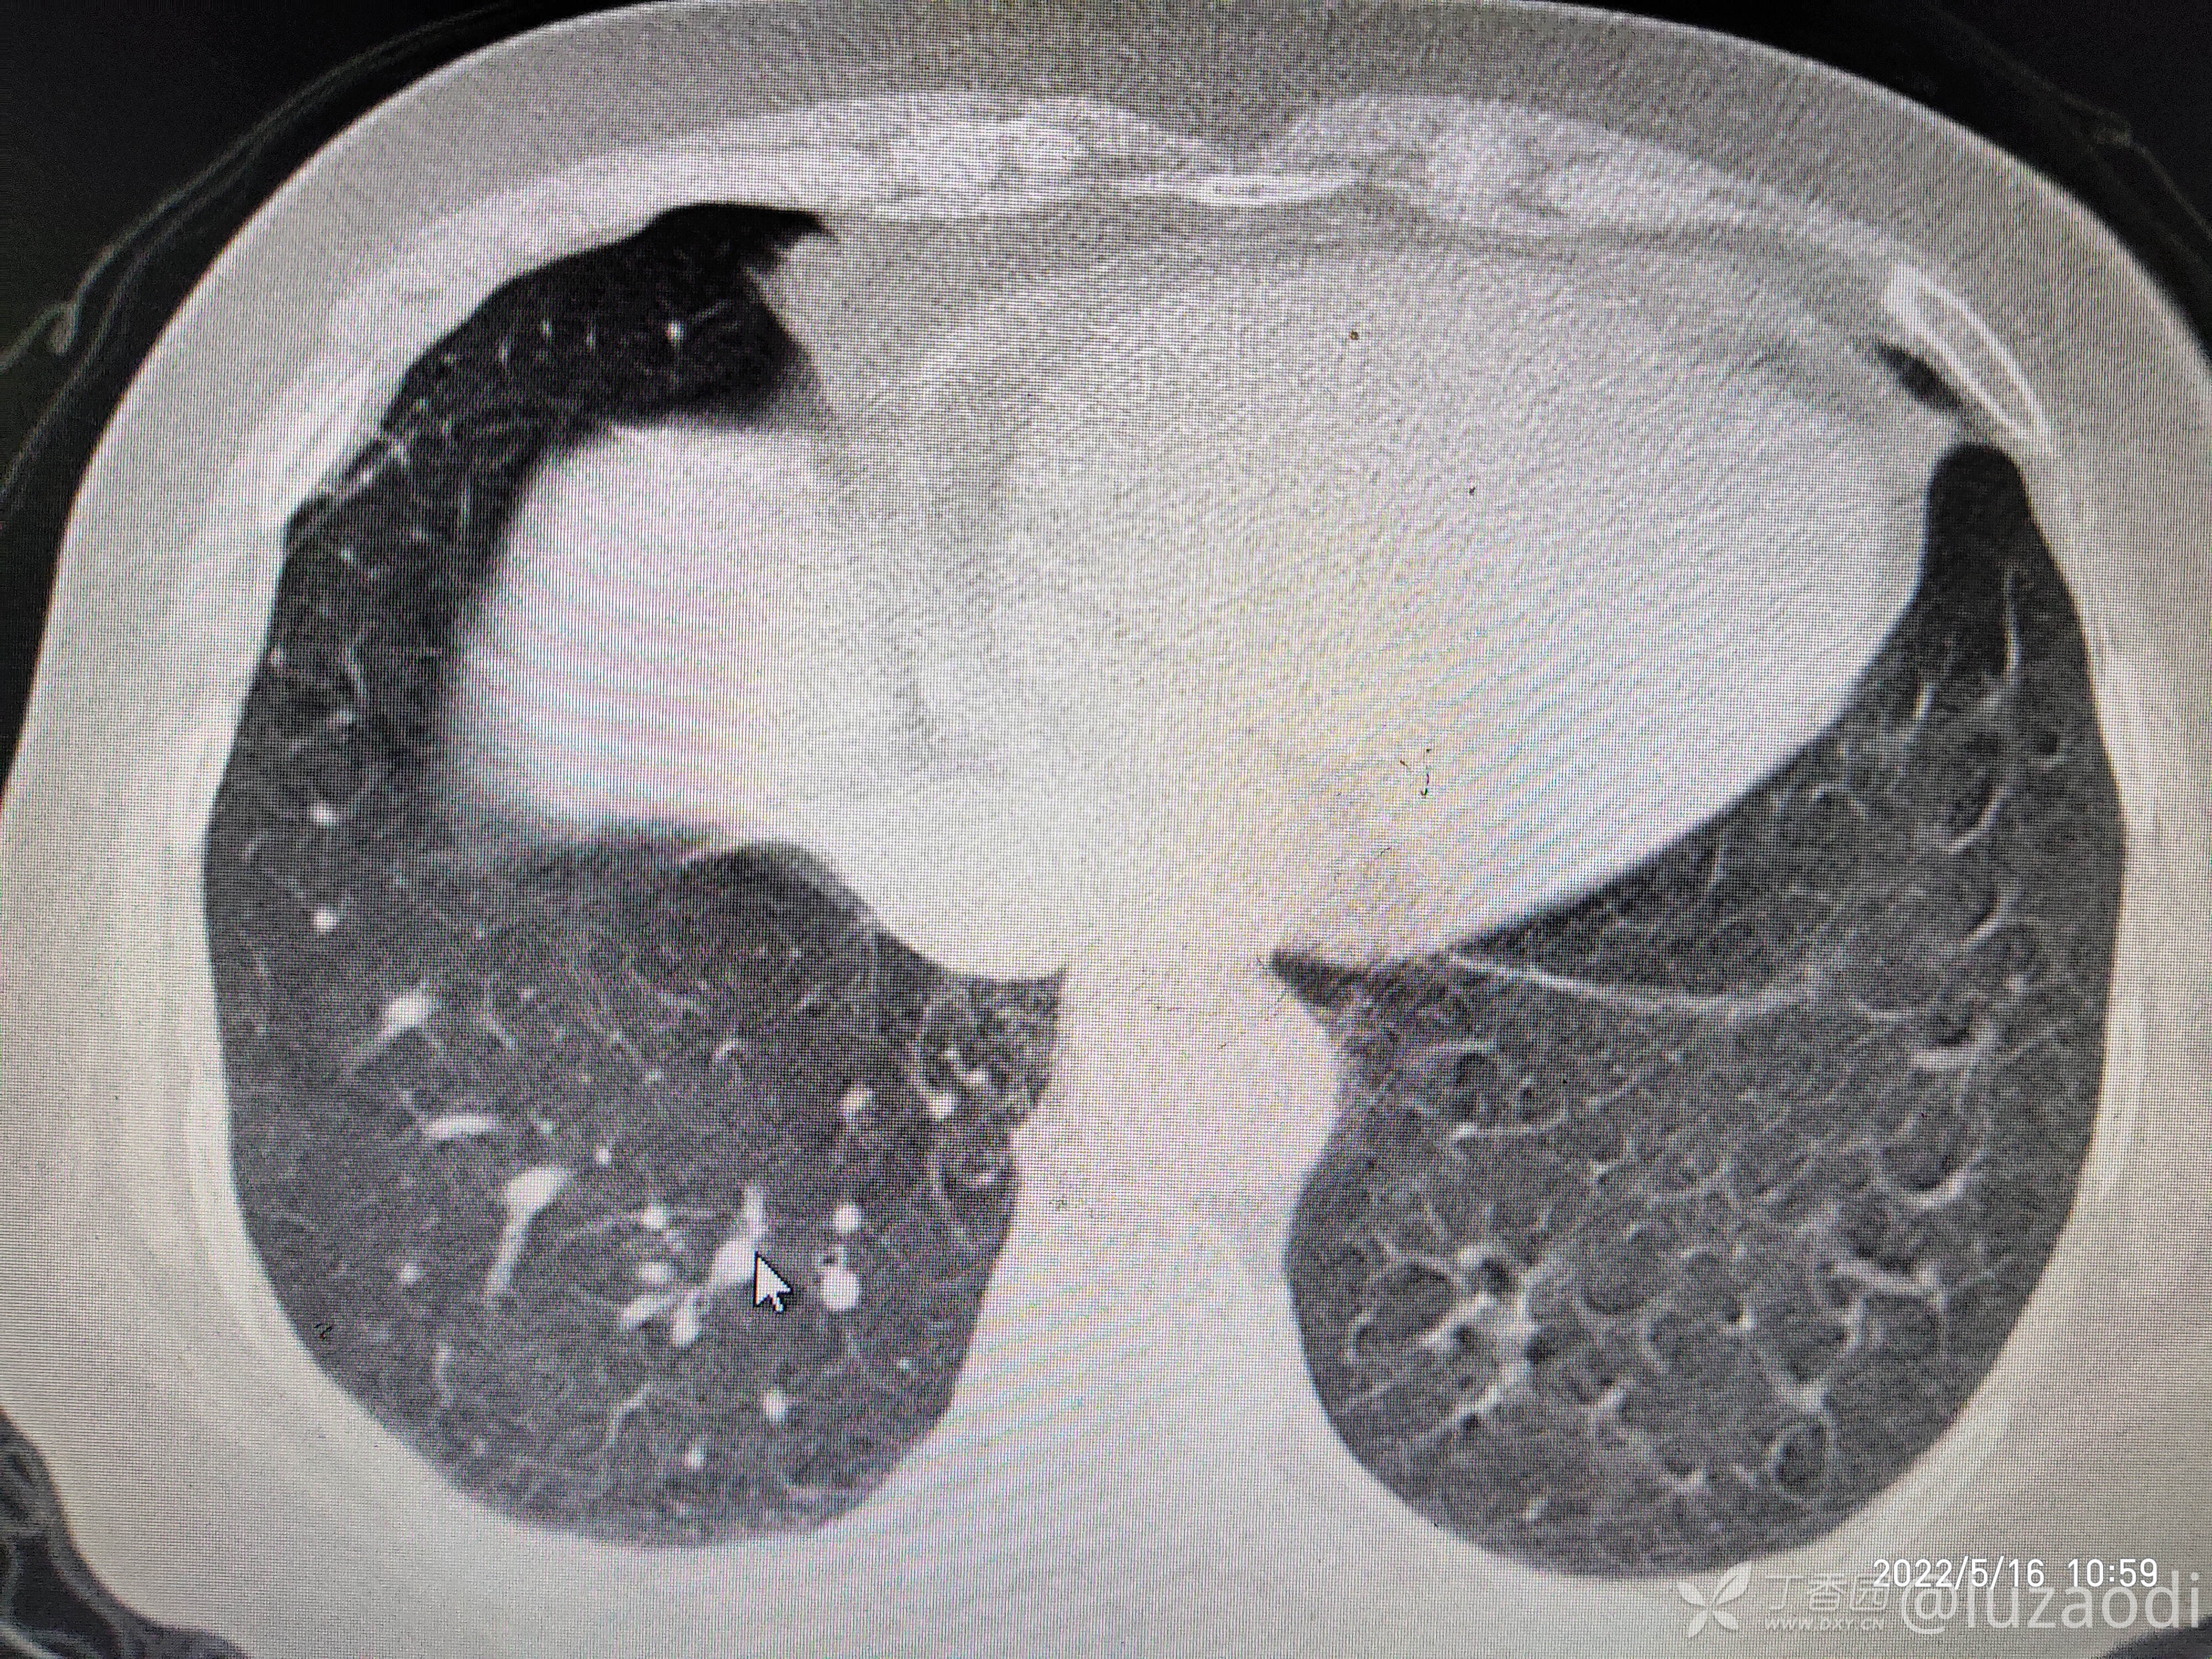

治疗经过:入院后患者仅有乏力,未见明显神经定位征。近期无发热、咳嗽、腹泻症状。遂予血糖、心电图、生化检查及影像检查,结果如下:

我去。。。。。视频只能上传一个,头颅CT上传不了,我直接说报告吧。头颅CT报腔隙性脑梗。